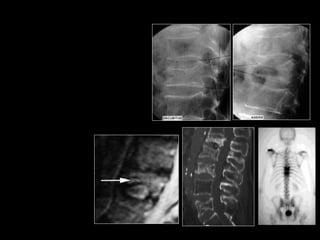

MRI of Acute Compression Fracture

T8

Plain film

T2W

T1W post-Gd

showing a significantly enhanced T8 indicating a recent fracture.

T9 is a chronic fracture and does not need vertebroplasty.

Pre-Operative Bone Scan

• In patients who

cannot have an MRI

• In identifying which

fractures are more

acute in nature and

most likely to

contribute to the

patient’s symptoms.